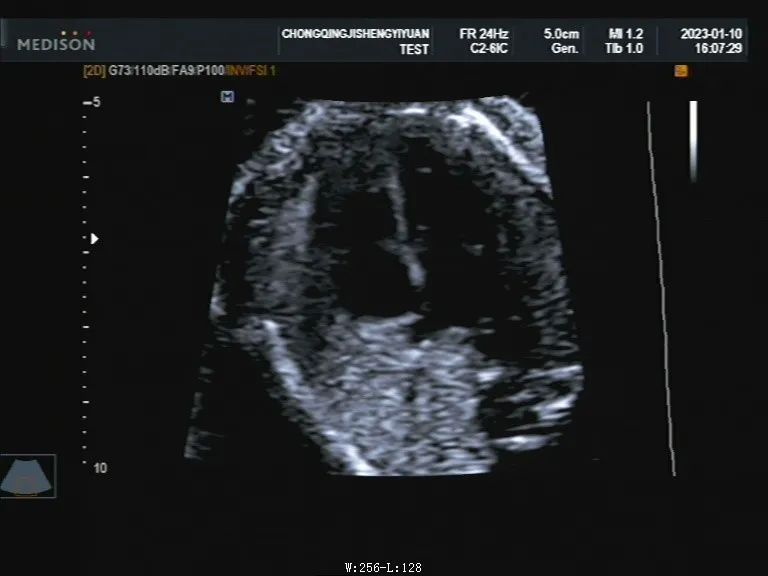

实际上我们多数非医学专业人士眼中的“黑白超”,就是B型超声,简称“B超”。超声的基本成像原理是将声束在传播途径中遇到各个界面时所产生的一些反射回声,在示波屏时间轴上以光点的灰度表达出来,而界面回声的强弱关系则由灰阶表示,这是属于一种灰度调制型的二维图像,反应在图像上就是黑白明暗的变化,通过图像可以识别人体结构。B超并不是低端的代名词,它是一切超声检查和诊断的基础。

B超胎儿心脏